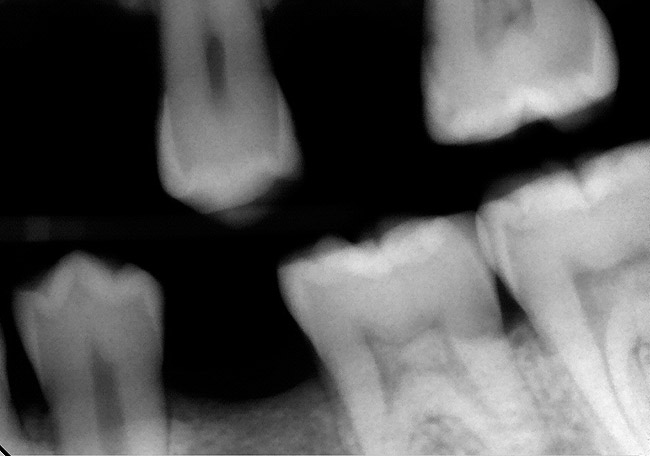

Figure 8A Evidence of deep caries on bitewing radiograph for tooth No. 14.

Figure 8A

Figure 8B No evidence of periapical pathology for tooth No. 14.

Figure 8B

Figure 8C EPT of tooth No. 14 reveals a high reading.

Figure 8C

Figure 8D Removal of caries reveals necrotic pulp (no frank bleeding when the pulp was exposed.

Figure 8D